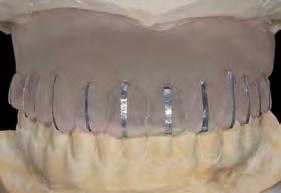

Figura 11­12. Prueba del encerado para la realización de la prótesis provisional tras 6 meses desde la colocación de los implantes. Figura 13. Radiografía panorámica tras la colocación de prótesis provisional de carga progresiva. Figura 14 y 15. Planificación por CAD/CAM de la estructura de la prótesis definitiva y finalización de la misma con el cementado de coronas de disilicato sobre la estructura.

La evidencia de que los implantes cortos ferulizados pueden presentar una predictibilidad similar a la de los implantes de mayor longitud, con un comportamiento biomecánico

Dentista y Paciente 54 Enciclopedia odontológica